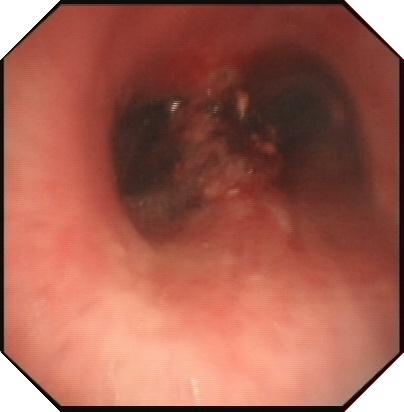

病例2 恶性肿瘤所致气管狭窄

理结果:鳞癌.